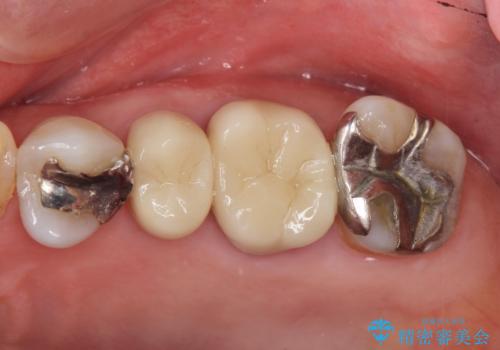

左上56間が狭かったため、写真にはないですが、セパレーションを2回ほど行い、歯根間距離を広げてから処置を行っています。

歯と歯の間(特に歯根と歯根の間)が異常に狭いと歯型が正確にとれない上に歯間ブラシも入らないような歯の形態になり、セルフケアに支障がでてきます。

そのまま無理やり歯型を取って製作するよりも、ご自身で清掃ができる形態にできるため、長期的な予後が期待できます。